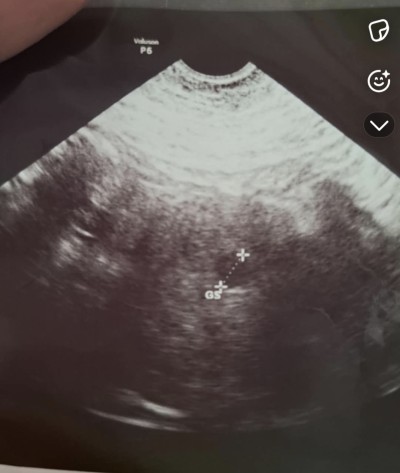

Canim benimki de bir benzerini yaşıyorum suan son adet günüm 21 Eylül kese ekranda zor gözüküyor resmen o kadar küçük ve belli belirsizki anlatamam en son 6+4 de gittim bebek yeni oluşmuş dedi ekrandan kalp atışını görüyorum ama makineye vurdu hiçbir şey duyulmadı bana da 1 2 hafta sonra gel dedi bir sorun var mi dedim bir sorun bence yok dedi kanama filan olursa gel dedi ama şükür bir şeyim yok bende suan 7+6 m 9+1 e denk geliyo gideceğim zaman inşallah o zaman duyarım bende senin gibi merak ve beklenti içindeyim inşallah hayırlı haberler alırız oglumda igne ile olmuştu gunu gününe uyumluydu bu doğal kendiliğinden oldu saglik ocağı hemsiresine sordum ovulasyonun gec olmuştur takılma boyle şeylere dedi benim bebeğim de 3 mm çıkmıştı bak kese ve bebeğin görüntüsünü koydum profilimde en altlara inersen oğlumun kesesi de gözüküyor ama o cok belli ve ikisi de aynı doktor